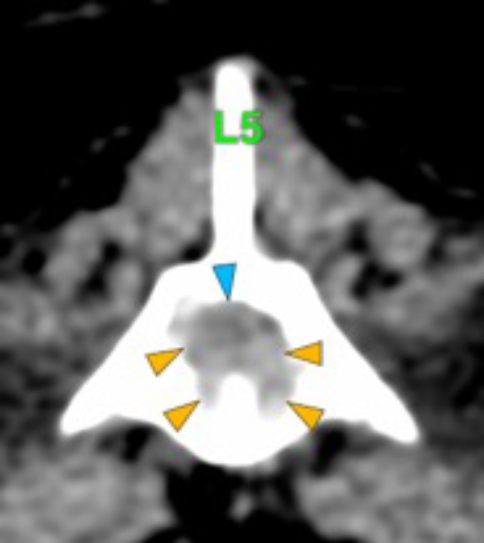

The osteolytic lesions have soft tissue attenuation that shows moderate and slightly heterogeneous post-contrast enhancement. In some of the vertebrae, the lesions cause lysis of the cortex and extend into the vertebral canal (orange arrows) causing variable degree of compression of the spinal cord and cauda equina (blue arrows). At the level of the vertebral bodies of T7, T8, T9 and T12 the lesions extend into the ventral and central aspect of the vertebral canal causing a mild compression of the spinal cord. At the level of T13, L1, L4 and L5 the lesions extend into the ventral and central aspect of the vertebral canal, causing moderate compression of the spinal cord. At the vertebral body of L6 the lesion extends into the ventral and central aspect of the vertebral canal, at the mid-aspect of L6, occupying approx. 90% of the diameter of the vertebral canal causing a severe compression of the cauda equina. At the level of L7, the lesion extends into the ventral and both lateral aspects of the vertebral canal, causing severe compression of the cauda equina.